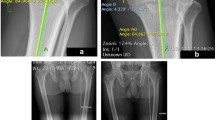

KSS 2011 scores except patient expectation were significantly improved postoperatively (Table 1). The average preoperative extension angle was significantly improved postoperatively, and preoperative flexion angle was maintained at 2 years after TKA. Regarding limb, femoral and tibial alignment, neutral alignment was achieved postoperatively. Preoperative alignment had no significant correlation with postoperative alignment in HKA (p = 0.166), FMA (p = 0.540), and TMA (p = 0.501) (Fig. 2).

The average residual varus–valgus imbalance was 2.8° (SD = 2.8°) varus in extension and 1.3° (SD = 4.0°) varus in flexion. The average varus–valgus angles were kept varus in extension and flexion, respectively (Fig. 3). The average extension gap was smaller than the flexion gap. The average extension and flexion gaps were 9.4 mm (SD = 2.5 mm) and 12.7 mm (SD = 2.8 mm), respectively. The average thickness of polyethylene insert was 10.0 mm (SD = 1.4 mm). The distribution of the laxity in flexion was more variable than in extension (Figs. 4, 5). Analyzing correlation with the alignment and the gap angle and joint laxity, the delta HKA angle had significant correlation with the joint gap angle, and the preoperative TMA and delta TMA had significant correlation with the laxity in extension (Table 2). Larger correction angle of limb alignment showed more varus joint gap in extension, and larger varus deformity and correction angle of the tibia showed more laxity in extension.

This study was conducted to evaluate our hypotheses using consecutive primary TKAs performed with a single implant design, in which prospectively collected data were retrospectively analyzed. All surgeries and gap measurements using a tensor device were executed, and clinical outcomes were evaluated at 2-year follow-up for 100 knees. Inclusion criteria were primary TKA for medial osteoarthritis of the knee using a ceramic tri-condylar posterior-stabilized implant (Bi-Surface 5: Kyocera, Kyoto, Japan) [20, 22, 23]. 17 patients presenting any valgus deformity were excluded from this analysis. Informed consent was obtained from all patients. The study design was approved by the institutional ethics review boards, and all procedures performed were in accordance with the ethical standards of the institutional research committee. A total of 15 male and 85 female knees with an average age of 75.7 years [standard deviation (SD) = 6.9 years] were included for surgery. The average preoperative hip–knee–ankle (HKA) angle, based on the angles between a mechanical axis of the femur and the tibia, was 11.5° varus (SD = 5.2°, range 0.6° to 24.5° varus). Ten knees had HKA smaller than 5°. The average preoperative femoral mechanical angle (FMA, the medial angle between the femoral mechanical axis and a tangent to the distal femoral condyles) and tibial mechanical angle (TMA, the medial angle between the tibial mechanical axis and a tangent to the proximal tibial joint surface) were 88.7° varus (SD = 2.5°) and 83.3° varus (SD = 2.7°), respectively. The delta values of HKA, FMA, and TMA between preoperative and postoperative alignment were calculated. The postoperative decrease of the varus deformity was denoted as positive. The average height and weight were 151.7 cm (SD = 6.9 cm) and 61.4 kg (SD = 11.0 kg), respectively, and the mean body mass index was 26.6 (SD = 3.9). Regarding statistical power, a post hoc power analysis was conducted because the data were retrospectively analyzed, in which the present study had 80% power to detect a parameter estimate of 0.3.